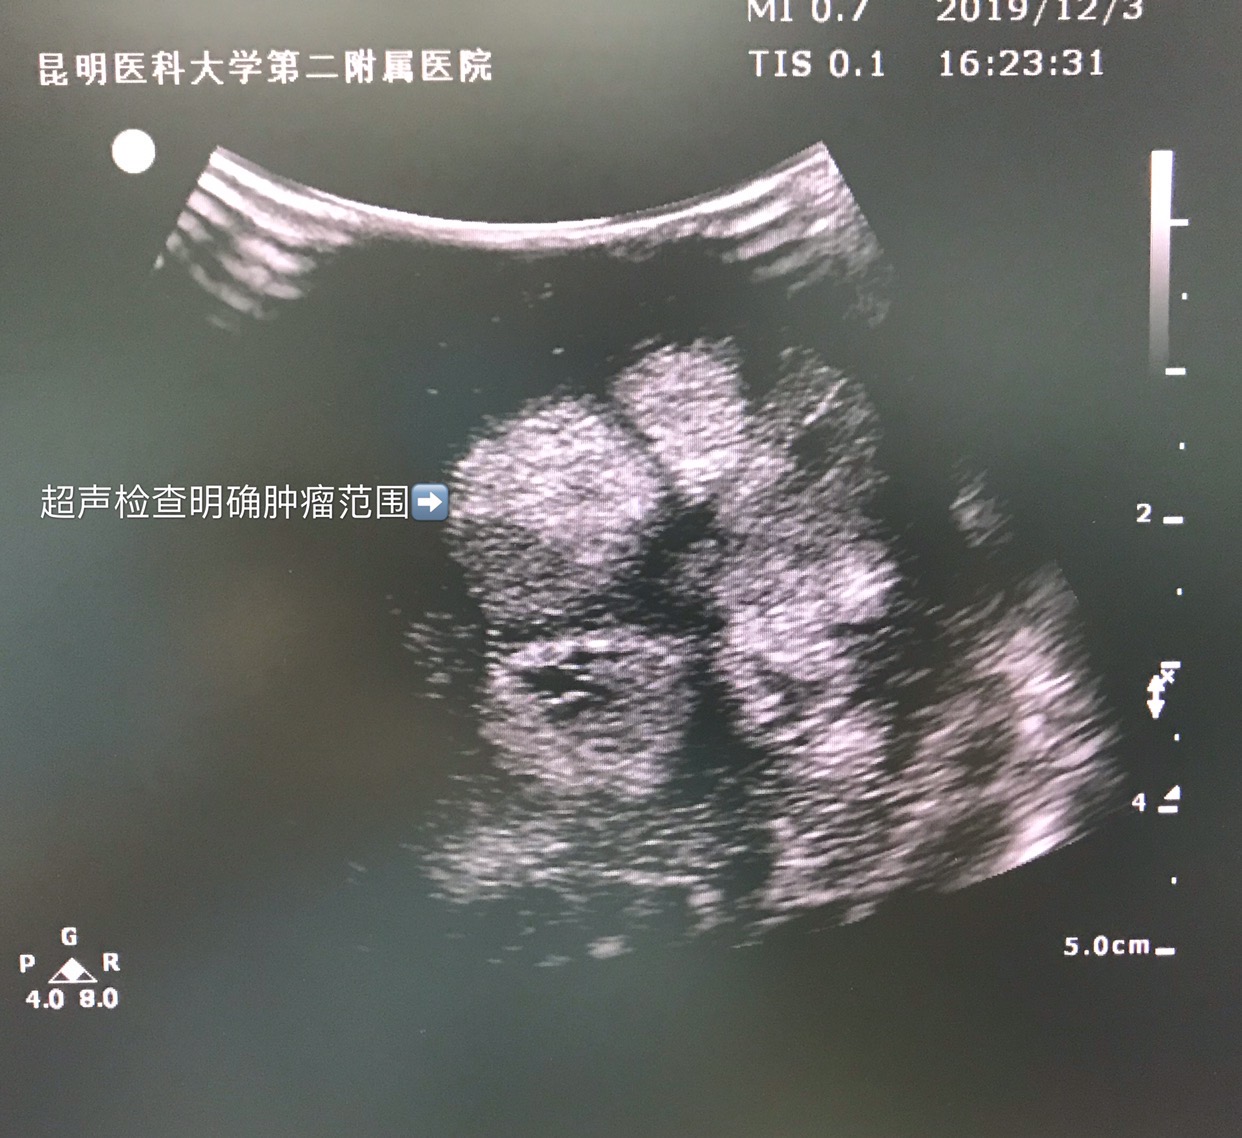

肿瘤为囊实性。

冠切面肿瘤超声影像。